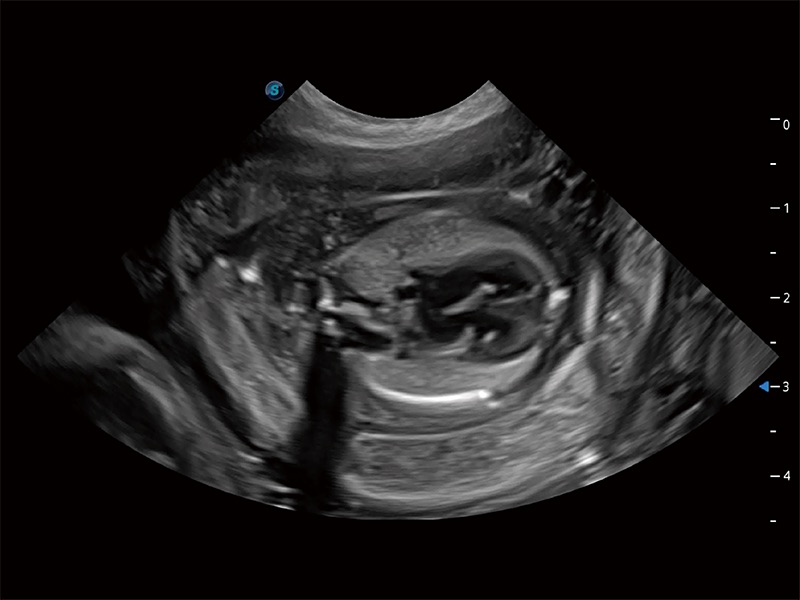

优异的基础图像

ProPet 80 全新的动物超声智能软件和丰富的探头群,为动物医生提供了高清晰度和精细分辨率的图像,无论在宠物、马科、畜牧还是实验室动物等应用中都可以轻松应对,为您的日常工作带来满意的体验。

(犬)胎儿四腔心